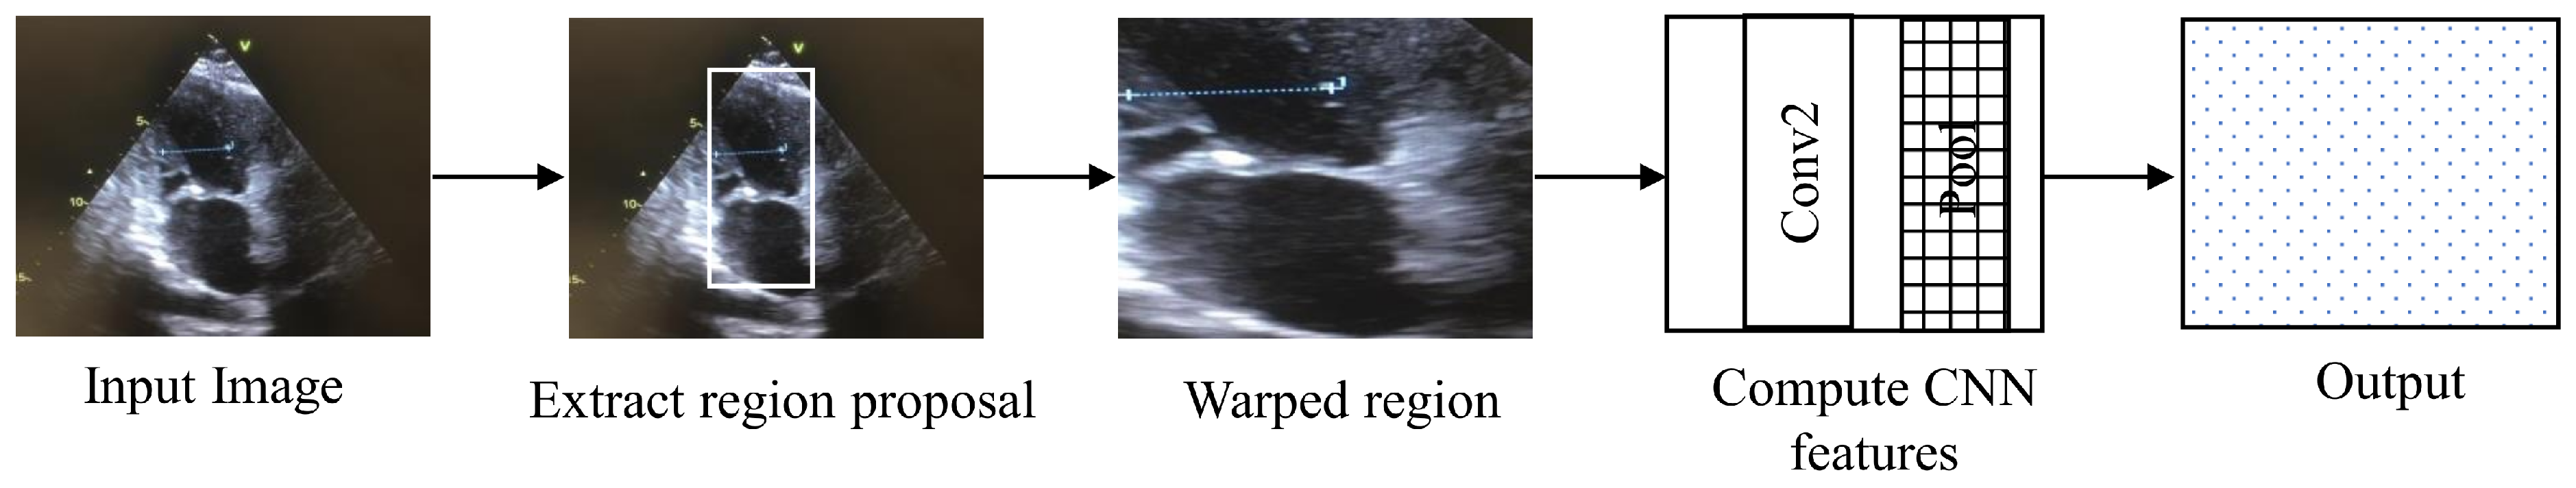

4.4. Regions with CNN Features

Regions with CNN features (RCNN) is an architecture used for segmentation and object detection. RCNN is called region-based because the input is divided into several regions to detect the object of interest, as shown in the Figure 6 [21]. RCNN takes around 45 s for processing per video frame, making it unsuitable for real-time application.